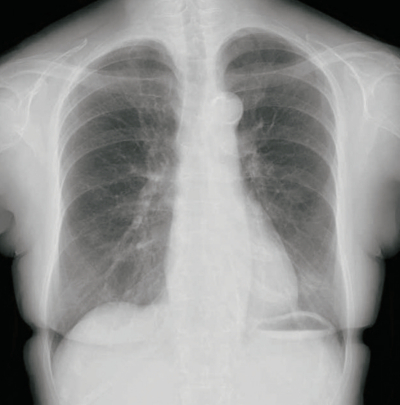

74歳の女性。胸部エックス線で異常陰影を指摘され来院した。3年前に直腸癌に対する手術を施行され、経過観察中である。昨年は異常を指摘されていない。胸部エックス線写真及び胸部造影CTを別に示す。